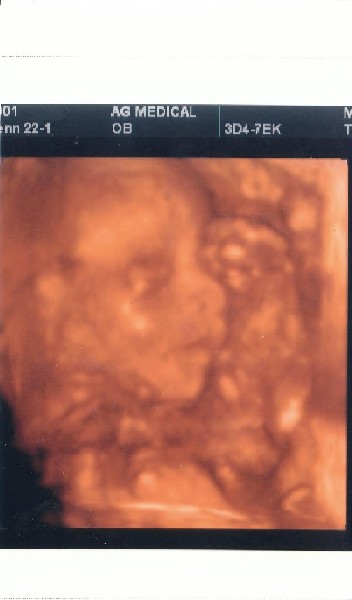

Megvagyunk a 4D-vel, minden rendben van. A mért adatok alapján 6 nappal fiatalabb mint a mensis számítás alapján.

Ébren volt, az egyik keze végig ott volt az arca környékén, nyújtogatta az ujjait, olyan volt mintha számolt volna. Aztán egyszer csak az egyik lábát is odatolta a fejéhez. Nyitogatta a száját (kortyolt), és ásított is.

Sajna a nemét 1000 %-osra ismét nem tudta megmondani, mert a lábait nagyon maga alá húzta. Többször is visszament hogy megnézze, aztán a végén azt mondta hogy inkább csajszinak tűnik, de nem meri totál biztosra mondani.

Úgyhogy a lényeg hogy minden rendben van, a hasi szervek, az agy, a méretek-arányok, stb. stb.

Aszonta a doki nő, hogy a legjobb a 30. hét környékén csináltatni a 4D-t, mert az arca ekkor néz ki szinte 100 %-ban úgy mint a születéskor. Utána már azért nem, mert annyira kicsi lesz a hely odabent hogy gyűrődik, összenyomódik az arcocskája.